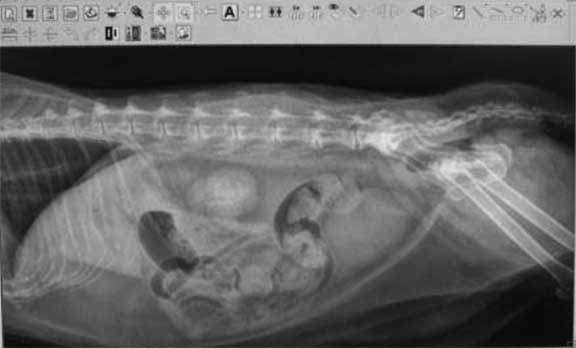

Radiographs (X-rays)

This is the radiograph of a dog with parvo virus

If you would like to learn how to read a radiograph we have a learning page called “How to Read a Radiograph“.